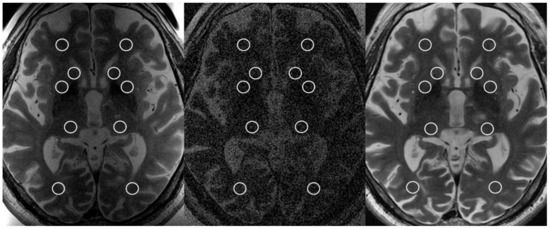

| 2ch-FUS SNR | Body-RF SNR | 8ch-HEAD SNR | p Value 2ch-FUS vs. body-RF | p Value 2ch-FUS vs. 8ch-HEAD | ICC (95% CI) | |

|---|---|---|---|---|---|---|

| Reader 1 | 10.54 (9.05, 12.61) | 2.96 (2.77, 3.31) | 16.24 (13.10, 19.95) | <0.001 | <0.001 | 0.85 (0.78, 0.89) |

| Reader 2 | 9.52 (7.74, 11.36) | 2.99 (2.83, 3.26) | 13.24 (10.67, 18.31) | <0.001 | <0.001 |